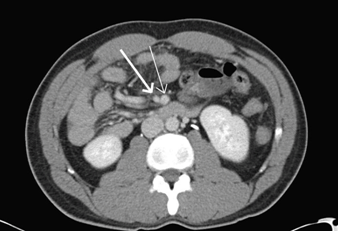

Variation in locality of tenderness and uncertain diagnosis required further investigation; a computed tomography scan of abdomen and pelvis. Imaging demonstrated marked dilatation of the appendix and periappendiceal fat stranding, confirming acute appendicitis (Figure 1). Non-rotation of the midgut was also noted, with the appendix and cecum was located in the left lower quadrant, and the majority of small bowel seen on the right side of abdomen (Figure 2). No bowel obstruction was present. The patient was commenced on intravenous antibiotics and preceded to theatre for emergency appendicectomy.

Figure 2: Axial computed tomography slice showing the superior mesenteric artery placed to the right of the superior mesenteric vein.